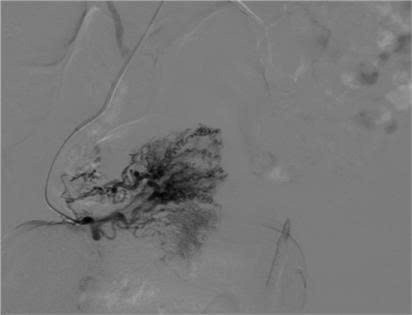

Bệnh nhân ngay lập tức được chuyển sang hội chẩn tại Trung tâm Can thiệp mạch – Bệnh viện Việt Đức. Kết quả chụp mạch số hóa xóa nền (DSA) xác nhận chẩn đoán ban đầu chính xác, đồng thời tiến hành nút mạch tại các vùng mạch máu tổn thương.

Siêu âm là một phương tiện đầu tay hiệu quả để chẩn đoán cũng như tiên lượng các tổn thương AVM. Chụp mạch máu số hóa xóa nền (DSA) là tiêu chuẩn vàng trong chẩn đoán AVM và đồng thời việc nút chọn lọc các mạch máu tổn thương là biện pháp điều trị hiệu quả cho bệnh nhân.